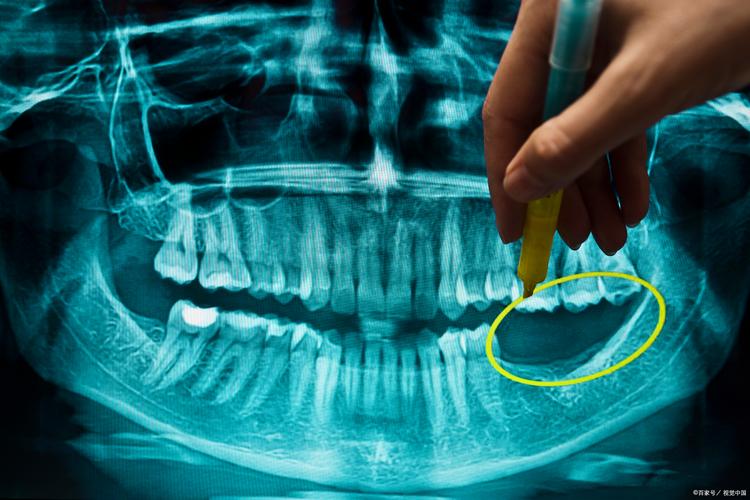

- 颌骨囊肿、肿瘤及瘤样病变: 精确定位、评估范围、与重要结构关系。

- 复杂牙髓病和根尖周病: 评估复杂根管形态、根管内器械折断、根尖周病变范围。